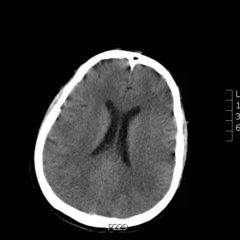

At the end of this module, the learner will be able to: 1) list the diagnoses critical to the emergency physician that may present with headache; 2) identify key historical and examination findings that help differentiate primary (benign) from secondary (serious) causes of headache; 3) discuss the indications for diagnostic imaging, lumbar puncture and laboratory testing in patients with headache; 4) recognize life-threatening diagnoses on CT imaging and CSF examination; 5) describe treatment strategies to relieve headache symptoms.

Headache, subarachnoid hemorrhage, migraine, occult trauma, meningitis, temporal arteritis, carbon monoxide toxicity, acute glaucoma, cervical artery dissection, space occupying lesion, idiopathic intracranial hypertension.